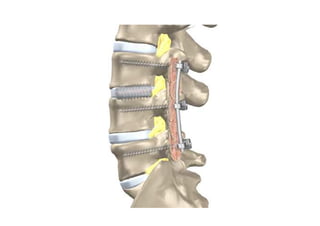

49- Cirurgia da hérnia discal lombar

50- Cirurgia da Coluna Lombar ( técnicas cirúrgicas)

51- Prótese discal lombar (artroplastias espinais de substituição – tipos de próteses)